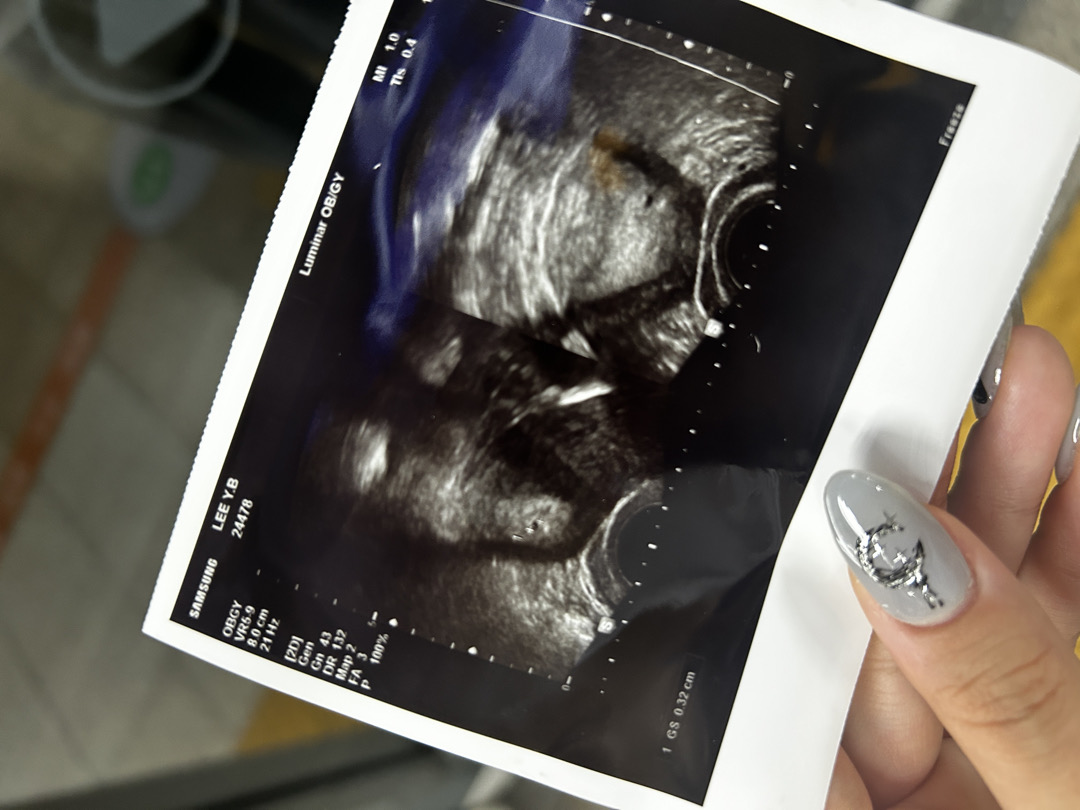

막생 5/29 시작이구 7/8에 초음파 봤는데 아기집이 많이 작아서 임신 확정은 아니라고 하시더라구요 ㅠㅠ 토요일에 다시 검사하기로 했는데 토요일이 너무 안오기도 하고.. 7/7에 임태기 했을때 완전 진한 두줄이라 다음날 아침에 바로 간건데 배도 적당히 참을정도로 아프고 가슴도 계속 아프네용 4주정도 된것 같다고 하셨는데 네이버나 다른 어플은 5주 6일인가 그렇다그러고 유산도 너무 신경쓰이는데 다들 그러신가요..? 저는 피비침이랑 열은 없는데 하얀냉이 많이 나왔습니다!